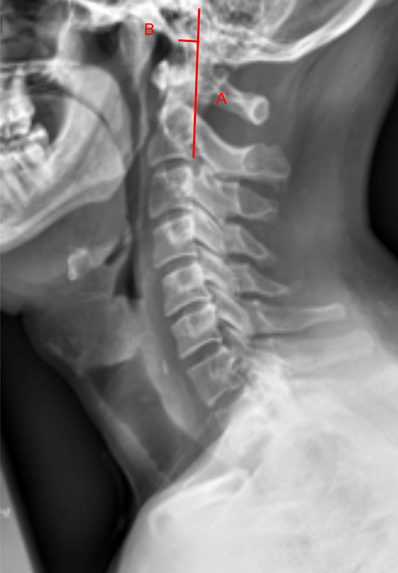

The Basion-Axial Interval (BAI), also known as the basion-posterior axial line distance, is a key radiographic measurement used to evaluate atlanto-occipital alignment and craniovertebral junction stability.

It measures the horizontal distance between the basion (the anterior margin of the foramen magnum) and a vertical line drawn along the posterior cortex of the dens (odontoid process) or posterior axial line.

This interval is particularly useful in detecting anterior or posterior translation of the occiput relative to the cervical spine, such as in atlanto-occipital dislocation (AOD) following trauma.

• Obtain a neutral lateral cervical spine X-ray (as shown in the attached image).

• Identify the following anatomical landmarks:

• Basion (B): The most anterior inferior margin of the foramen magnum.

• Posterior axial line (A’): A vertical line drawn along the posterior cortex of the odontoid process (dens) and extending inferiorly along the posterior surface of the body of C2 (axis).

• Measure the horizontal (anterior–posterior) distance between the basion (B) and the posterior axial line (A’).

• The measurement should be taken perpendicular to the posterior axial line, not along the skull base.

• Positive values indicate the basion lies anterior to the posterior axial line; negative values indicate the basion lies posterior to it.